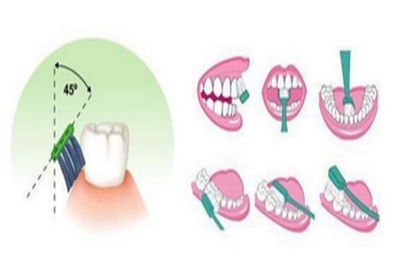

1。首先要做初步检查。医生会对口腔内的牙结石、牙菌斑,或者是否有牙周炎等进行治疗。,而且通常会先推荐使用一些辅助漱口水,所以如果有这样的建议,就要遵医嘱使用3~4天。但这种漱口水不能长期使用,只能短时间缓解和消除部分牙龈症状,然后才适合洗牙。2.洗牙后,牙齿会有一个短暂的敏感期,经常会让洗牙者觉得牙齿冰凉,甚至有的洗牙者会觉得牙齿变宽。这些都是去除牙菌斑和牙结石后的敏感特征。后来这种敏感症状会逐渐减轻,大部分需要一周左右。注意这段时间不要吃生冷硬的食物。

主要是由于牙龈退缩或酸蚀、磨耗等因素,表面釉质丧失,牙本质暴露,牙本质内有无数与牙髓神经相通的牙本质小管。当你吃冷热、酸甜的饮料和食物,甚至牙刷刷毛,并与牙本质接触时,就会发生牙本质过敏。牙齿敏感的原因1。刷牙方法不当用刷毛牙刷用力刷牙是常见的,这样会使牙齿的外层珐琅质磨损,牙龈萎缩,牙本质暴露。2.牙周病牙周病导致牙根萎缩。

如果冷、热、酸、甜的食物都能对牙齿造成刺激和疼痛,那么你可能已经转变为牙本质过敏的疾病了,那么牙本质过敏的原因是什么呢?1.口腔卫生习惯不当,如牙刷使用不当、刷牙方法不正确或用力过猛,造成牙釉质磨损、牙龈萎缩、牙本质暴露;2.吃酸性食物常导致牙面腐蚀和牙本质暴露;3、异常咬合,使牙釉质严重磨损,牙根因牙龈萎缩而外露。